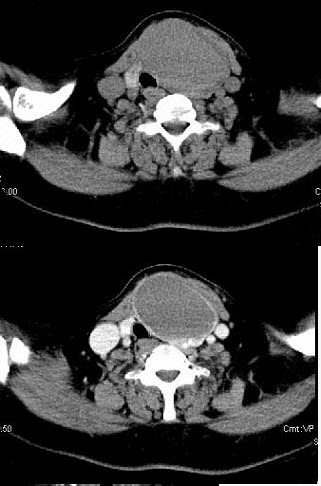

女,56岁,发现颈部肿块一月余,CT如图所示,最可能诊断为()。

A、甲状舌管囊肿

B、甲状腺乳头状癌

C、甲状腺原发淋巴瘤

D、甲状腺腺瘤

E、甲状腺脓肿

D